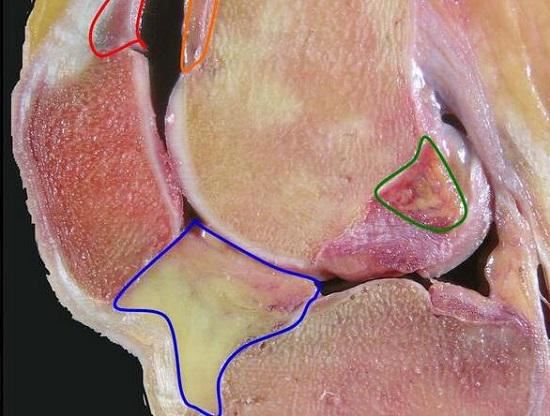

关节损伤不同于其他损伤。关节的特殊之处主要有如下三点。首先,关节的功能在于运动,而非静止和稳定。以膝关节为例,膝关节本身就是一个上、下两部分彼此分离的结构,其内部出现损伤后,需要愈合的是断面,而不是关节面,也不是交织在一起的关节囊、韧带和肌肉。不幸的是,组织的愈合常常不分彼此,暗月岛怎么去创伤出现后,新生的组织可能会将那些本应分开的组织牵连到一起,软组织粘连、异位骨化、关节僵硬等问题随之而来,膝关节将因此失去运动能力。所以,如果是急性损伤引发的疼痛,当急性损伤得到控制和解除后,膝关节一定要通过合理的方式运动起来,在梁羽生电视剧运动中让各个软组织各行其道、彼此独立,才能避免引发严重的后遗症。

僵硬的膝关节(纵剖面)